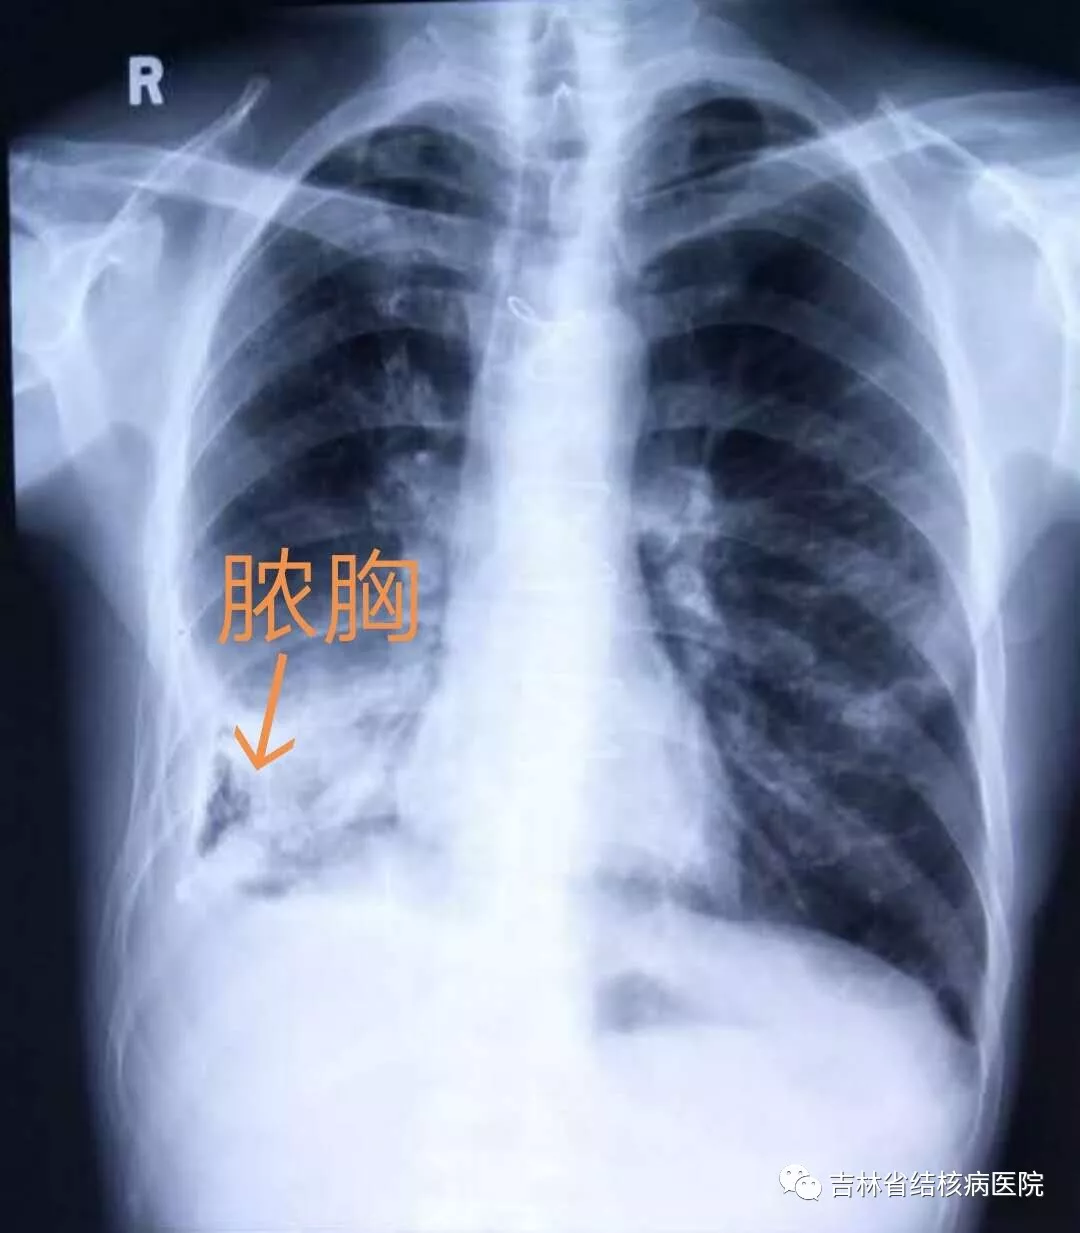

脓胸影像资料

答:首先脓胸不是胸膜炎,但是这两种疾病却有着密切的联系。当致病菌(80%以上是结核菌)直接或间接感染胸膜腔后,形成胸膜腔积液(也就是人们所说的胸水),这个时候就患了胸膜炎。病人可有咳嗽、胸痛、胸闷、发热等等,严重可伴有呼吸困难,很多人都把它当作“感冒”治疗或者根本不当回事,从而延误了治疗,就发展为脓胸,其中80%是结核性脓胸。结核性脓胸不但伴有上述症状,同时严重时伴有病侧的胸廓变形,影响呼吸功能。其中一部分病人脓胸范围较小或比较局限称之为包裹性脓胸,结核性脓胸如果不及时治疗将严重影响病人的日常生活及劳动能力。